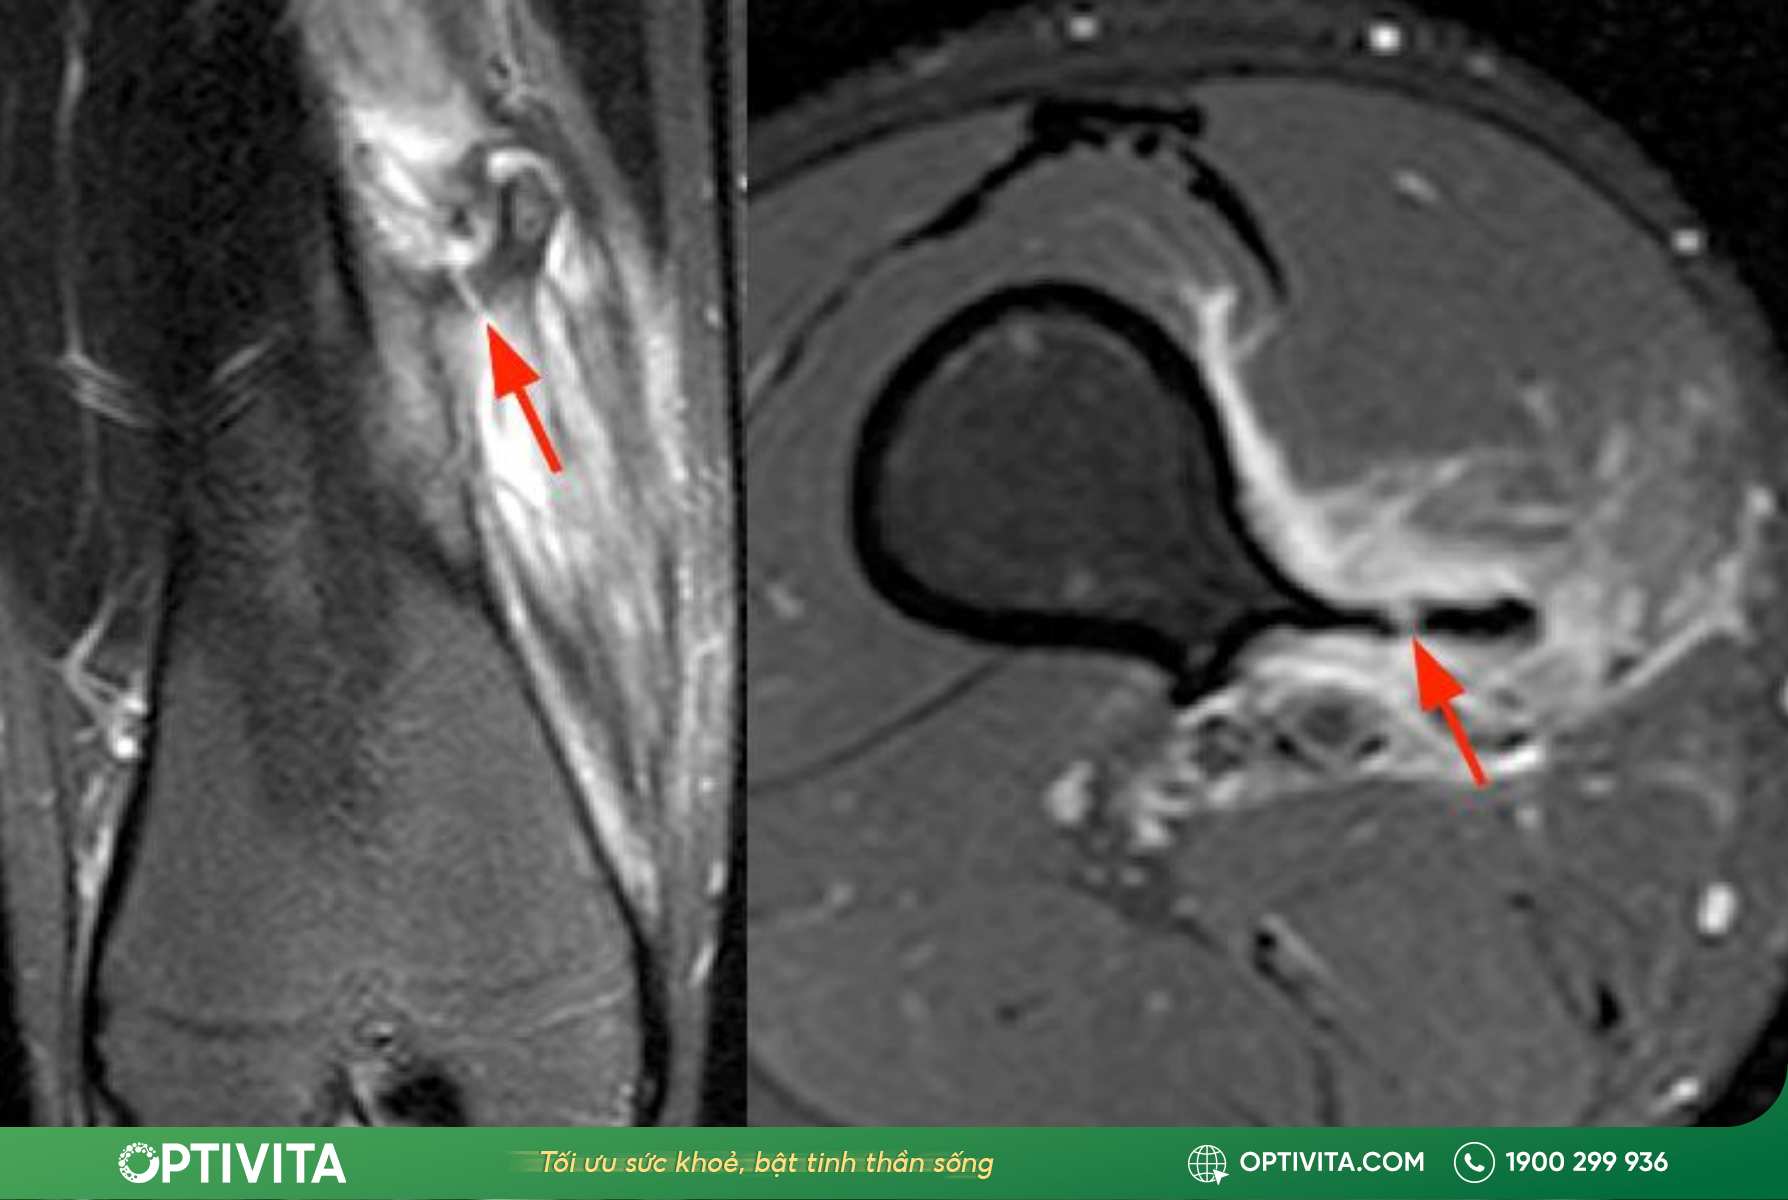

- Độ dày mũ sụn (Cartilage Cap) trên MRI > 2cm: Trên phim cộng hưởng từ, nếu lớp mũ sụn bao phủ khối u dày vượt quá 2cm, nguy cơ khối u đã chuyển sang giai đoạn ác tính là rất cao.

- MRI (Cộng hưởng từ): Nếu X-quang chỉ thấy được phần xương, thì MRI cho phép nhìn thấu cấu trúc mô mềm, đặc biệt là đo chính xác độ dày của mũ sụn. Như đã đề cập, nếu lớp mũ sụn này dày bất thường (trên 2cm ở người lớn), đây là tín hiệu cảnh báo nguy cơ ác tính cần sinh thiết ngay lập tức.